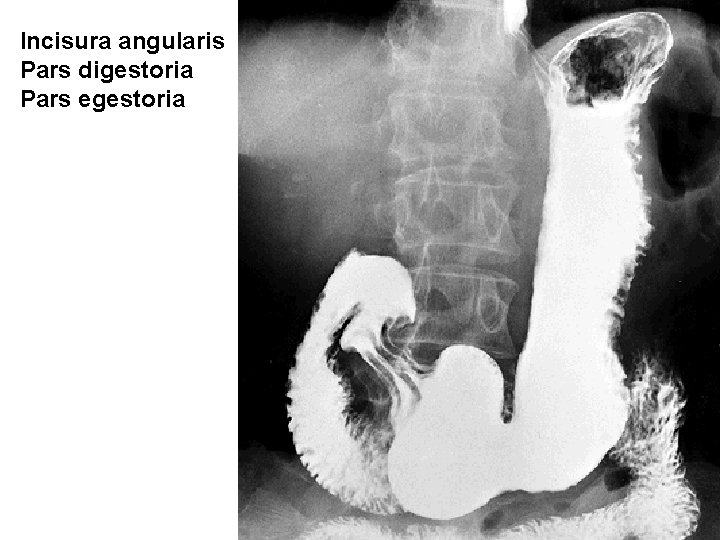

Incisura angularis Pars digestoria Pars egestoria